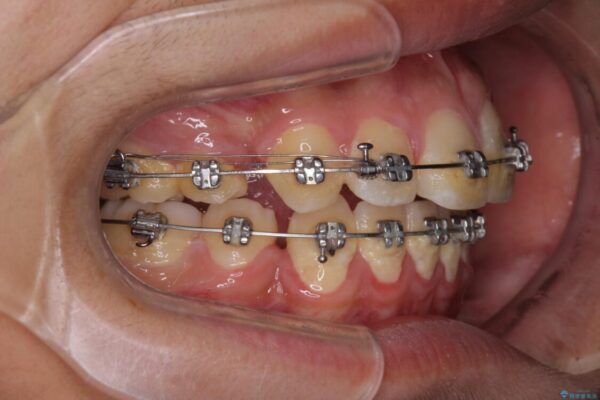

治療途中

• 膨らんだ口元 ワイヤー装置での抜歯矯正 治療途中画像